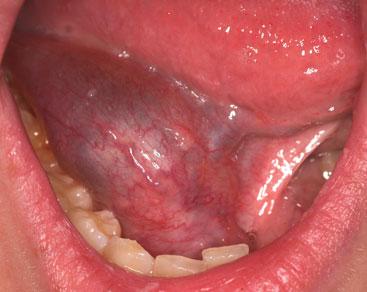

RANULA

The word ranula takes its origin from the Latin 'rana' meaning little frog. The condition is a mucocoele in the floor of the mouth. It most commonly develops in people between the age of 10-20 years, and results from the extravasation of mucous — usually from the sublingual glands — into the surrounding soft tissues. The problem may relate to trauma but often there is no known precipitating factor. A swelling may be felt in the floor of the mouth. It may disappear spontaneously, which is more likely in children. If aspirated, recurrence is common and the most successful surgical method is complete excision, including resection of the sublingual gland.